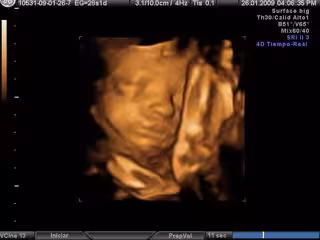

Ecografía en 3D- embarazo

Los investigadores analizaron las secuencias de vídeo 4D de 15 fetos sanos (ocho femeninos y siete masculinos) de entre 24 a 36 semanas de gestación para examinar de cerca todos los acontecimientos en un tramo de aftosa en el feto y hallaron que más de la mitad de las aberturas de la boca observadas fueron bostezos, según publica este miércoles la revista 'Plos One'. El bostezo se redujo desde las 28 semanas y que no hubo diferencias significativas entre niños y niñas en el bostezo frecuencia.